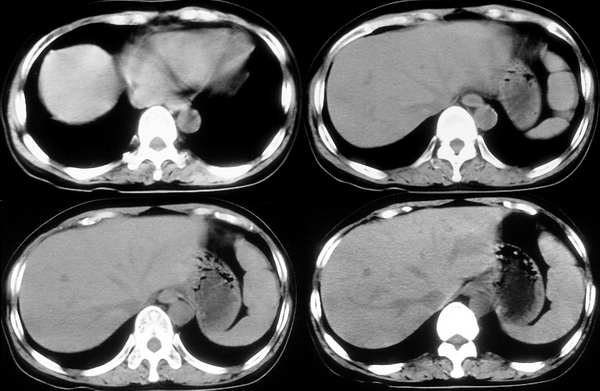

[br]请问战友,肝左叶低密度影和增强后杂乱无章的血管是什么?这是正常的吗?

以下是引用向医生在2005-11-3 21:54:00的发言:[br][br] 我觉得这例除了胆囊结石可以肯定外,肝左叶低密度区考虑为病灶尚不可靠。[br] 在b超下,早期肝脓肿者肝内见较强回声,界限欠清、模糊、形态不规则,如果有坏死液化才会出现低回声,而本例超声下已见低回声,如果真是这种情况的话就是说明病灶内已有坏死液化,这些液化区在ct增强下应该表现为低密度影,本例增强并无这样改变,所以b超的结果可不可靠值得怀疑。[br] 胆囊结石合并胆囊炎也可出现畏寒、发热及白细胞增高等,抗炎治疗后也可症状缓解,不一定非要用肝脓疡来解释。